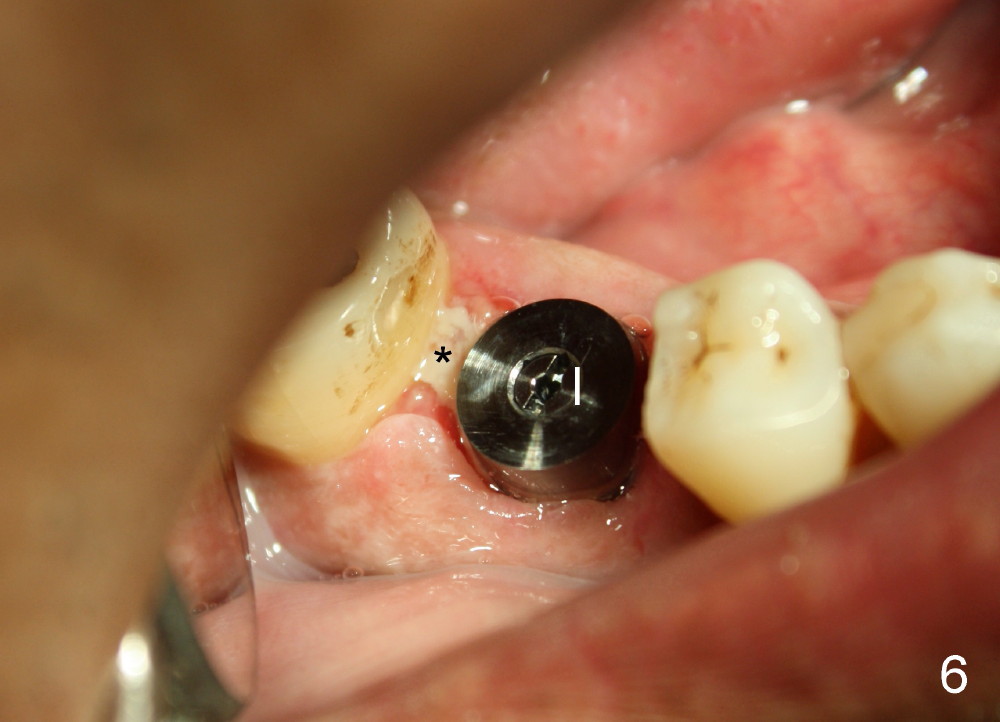

The patient returns for extraction and immediate implant after 7 days of oral Amoxicillin. There is a deep pocket mesiolingually in addition to the mesiobuccal fistula (Fig.1 <). The metal crown and then the tooth are sectioned. The crack of the mesial root is confirmed during extraction. The coronal portion of the mesiobuccal plate is defective, corresponding to the fistula. Both the mesial and distal sockets are large with a thin septum in between. Osteotomy is established at the base of the septum, slightly toward the mesial socket, as evidenced by a 5x20 mm tap in place (Fig.2). Finally, a 7x17 mm implant is placed (Fig.3 I; A: abutment; G: bone graft). The insertion torque is more than 60 Ncm.

Three weeks postop, the gingiva is healthy around the implant (Fig.5 I). There is no symptom or sign of the infection (>, as compared to Fig.1). The abutment has accomplished its transient function (A, the perio dressing having dislodged) and is subsequently removed (Fig.6, to reduce micromovement of the implant and cheek and tongue bite). The 7 mm implant (I) does not look too big in its new home (alveolus). Four months postop, the mesial socket appears to have normal bony trabecular patterns (Fig.7, as compared to Fig.3).